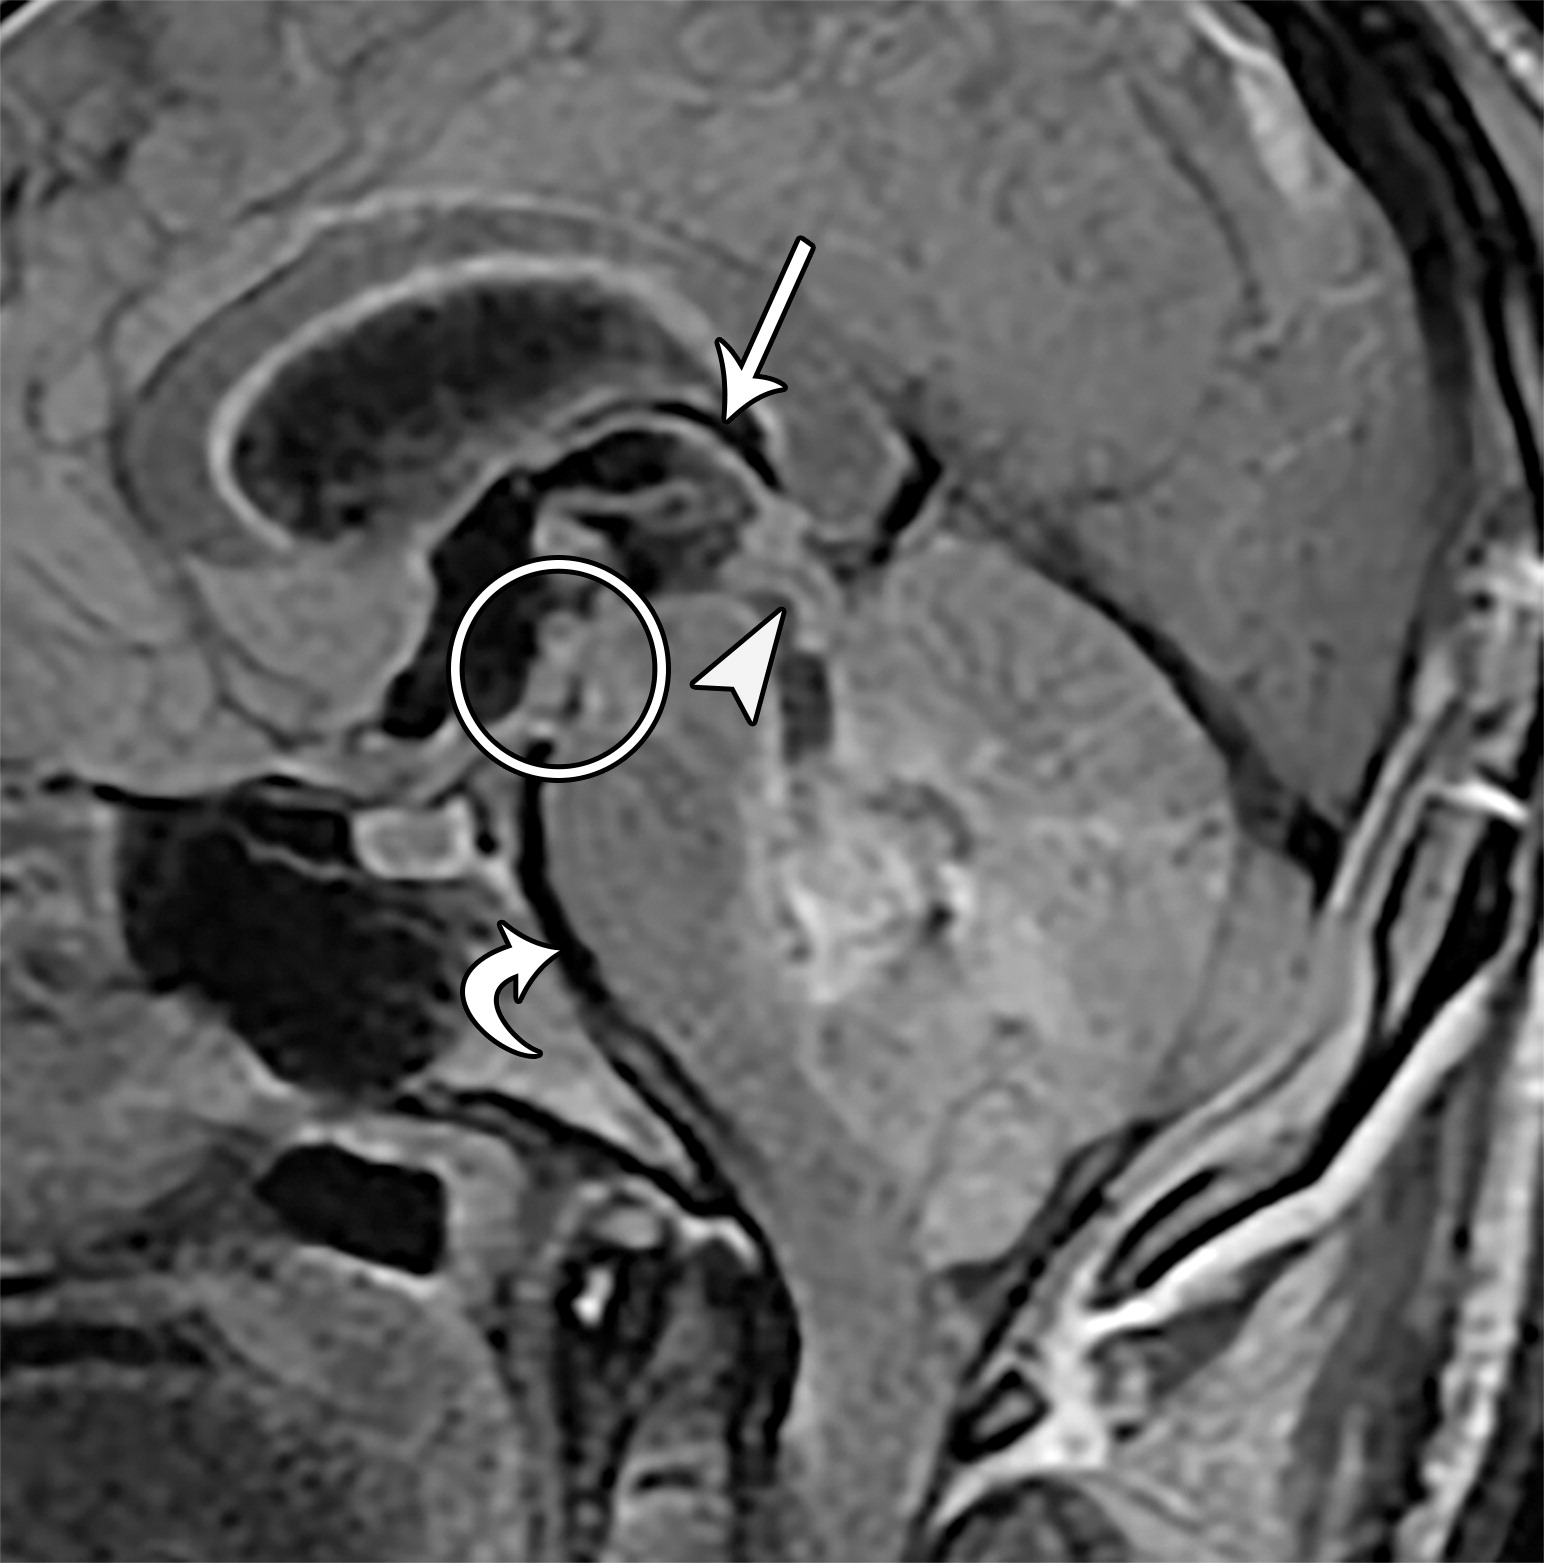

上升性小脑幕裂孔疝。26岁男性,切除髓母细胞瘤后。四叠体池,小脑上池,大脑脚间池的闭塞。下丘(白色短箭头)折叠于上丘的下方,且上丘及下丘两个结构均向上移位。脑干向前移位,导致脑桥池及延髓池间隙变窄(白色弯曲箭头),注意第三脑室顶的向上移位(白色长箭头),乳头体及灰结节向前移位并与中脑紧密相连(白色圆圈)。